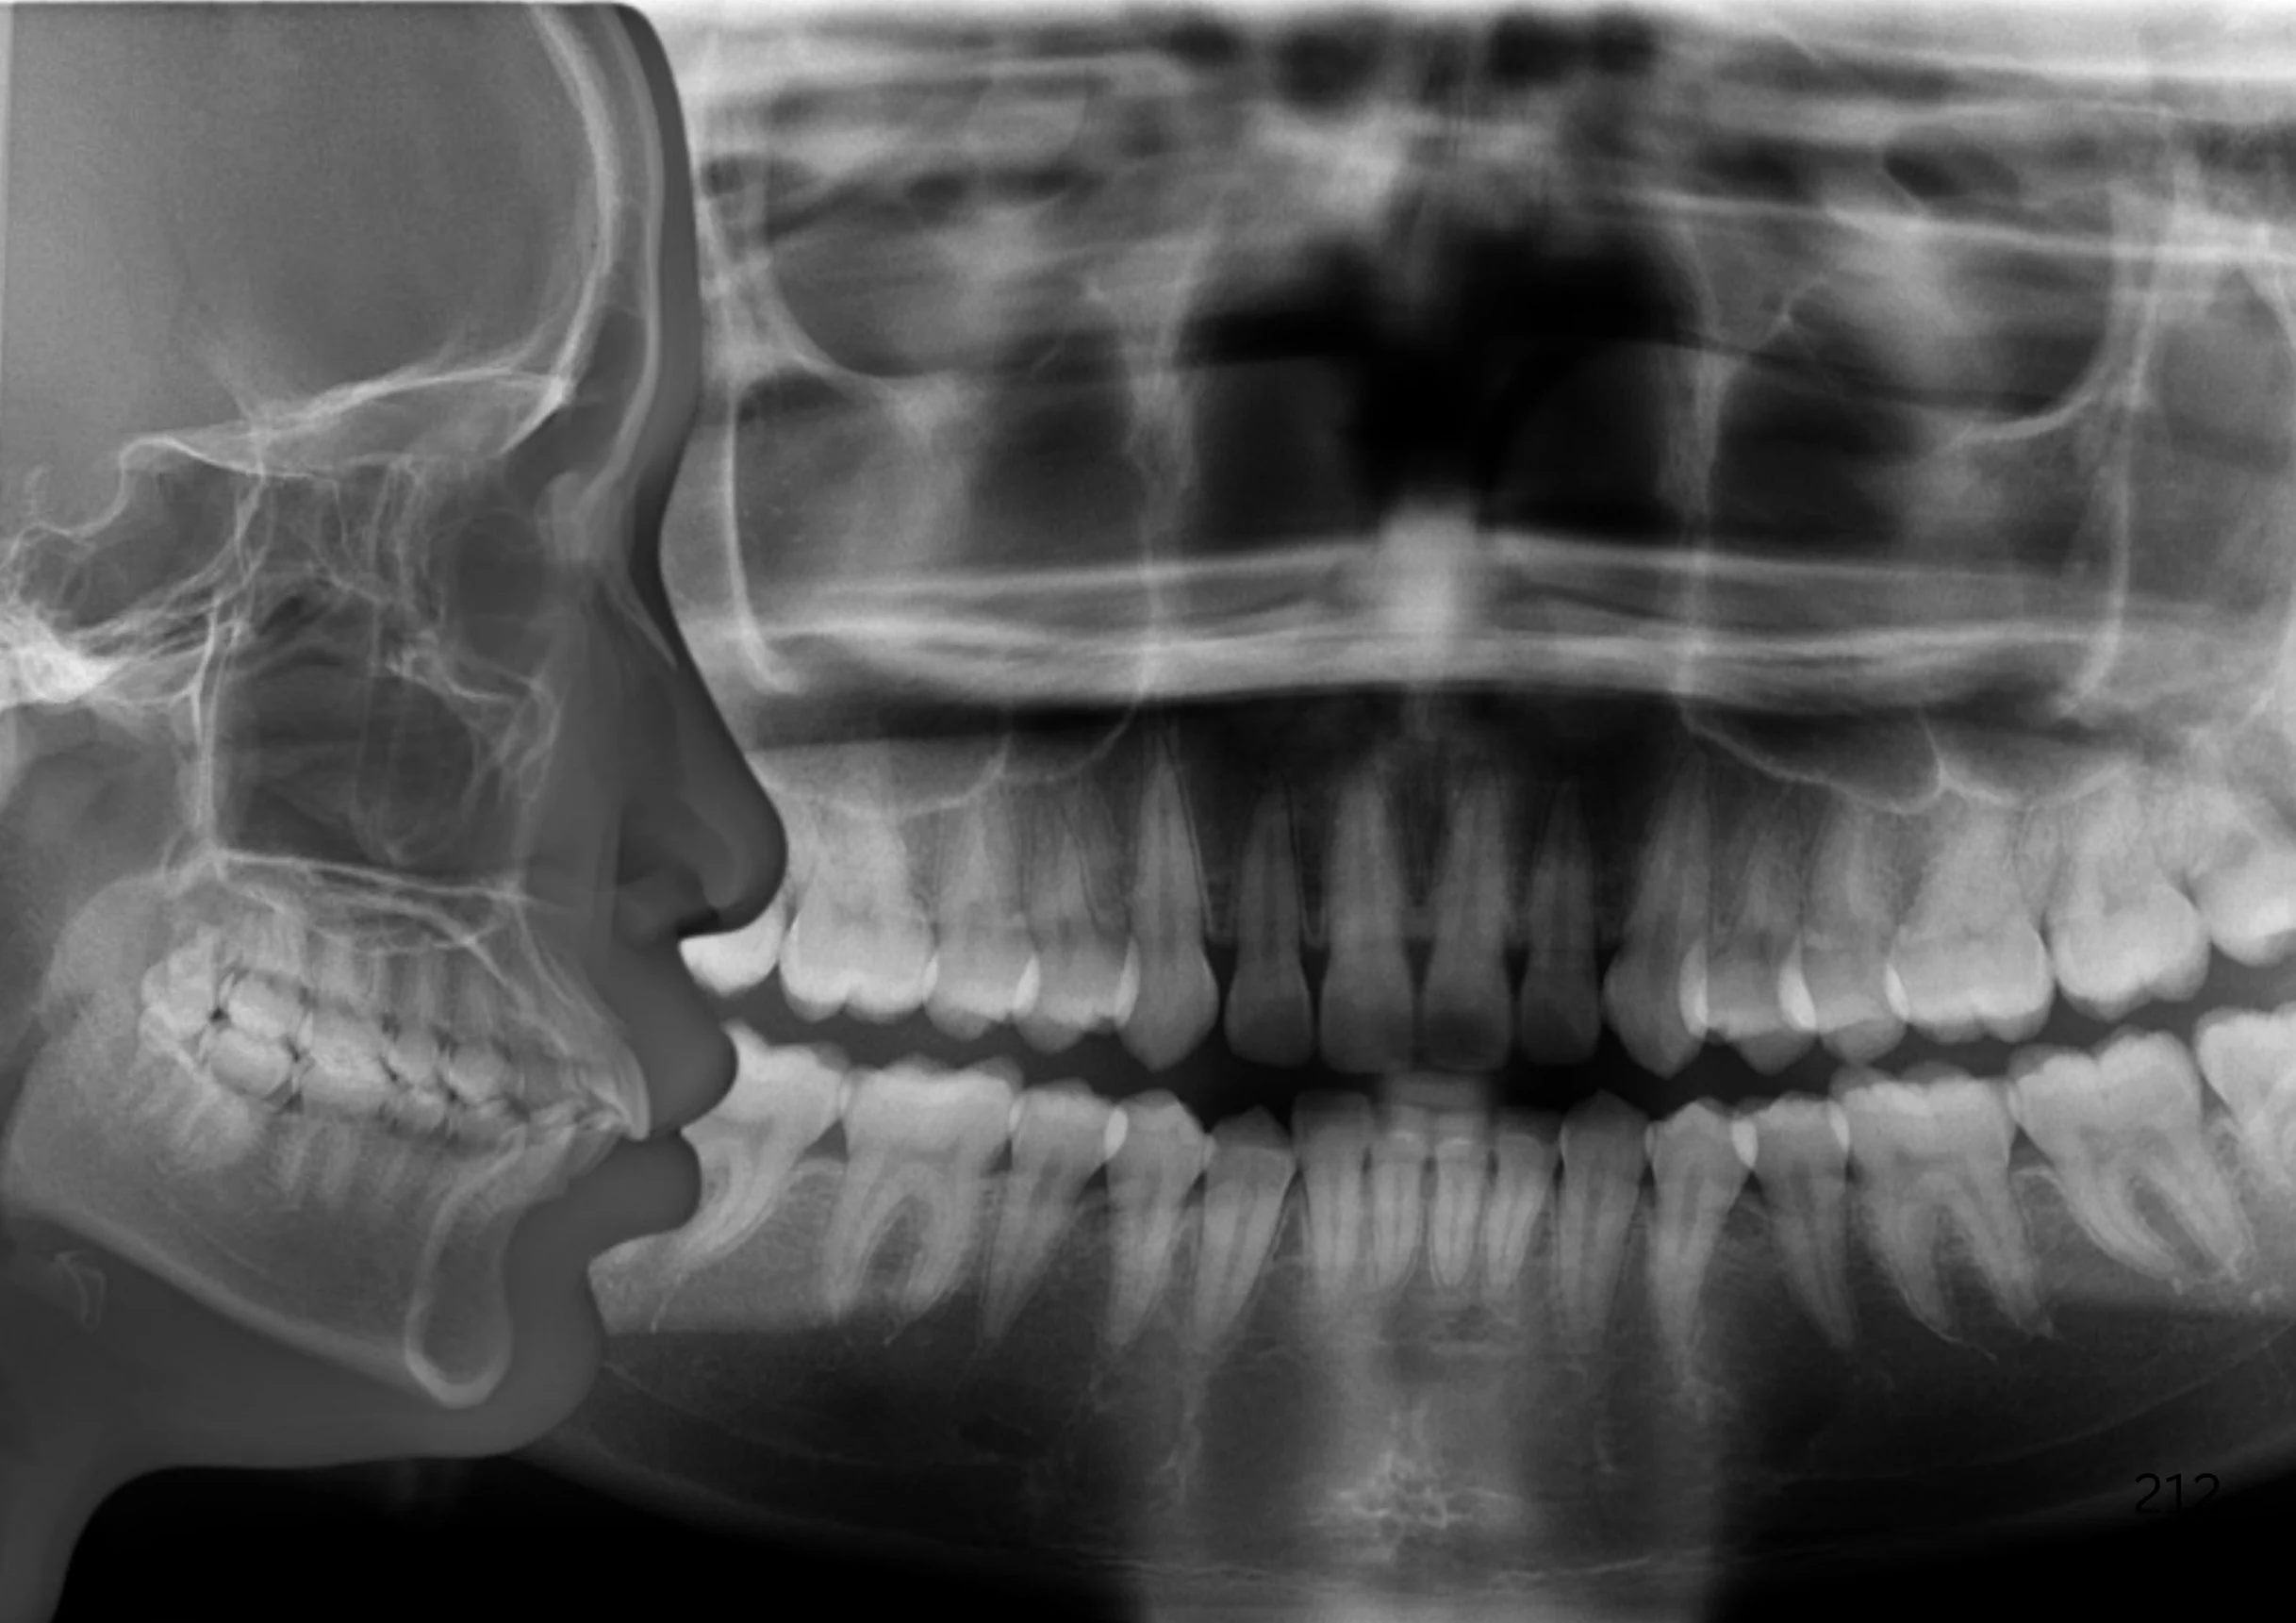

Before & After Invisalign® Gallery

Children aged 4–10 are in mixed dentition (a mix of baby and permanent teeth). Treatments at this stage are called Phase 1, focusing mainly on skeletal development with secondary attention to teeth alignment.

Once all permanent teeth have erupted (around age 11–13), Phase 2 treatment begins, focusing fully on teeth alignment.